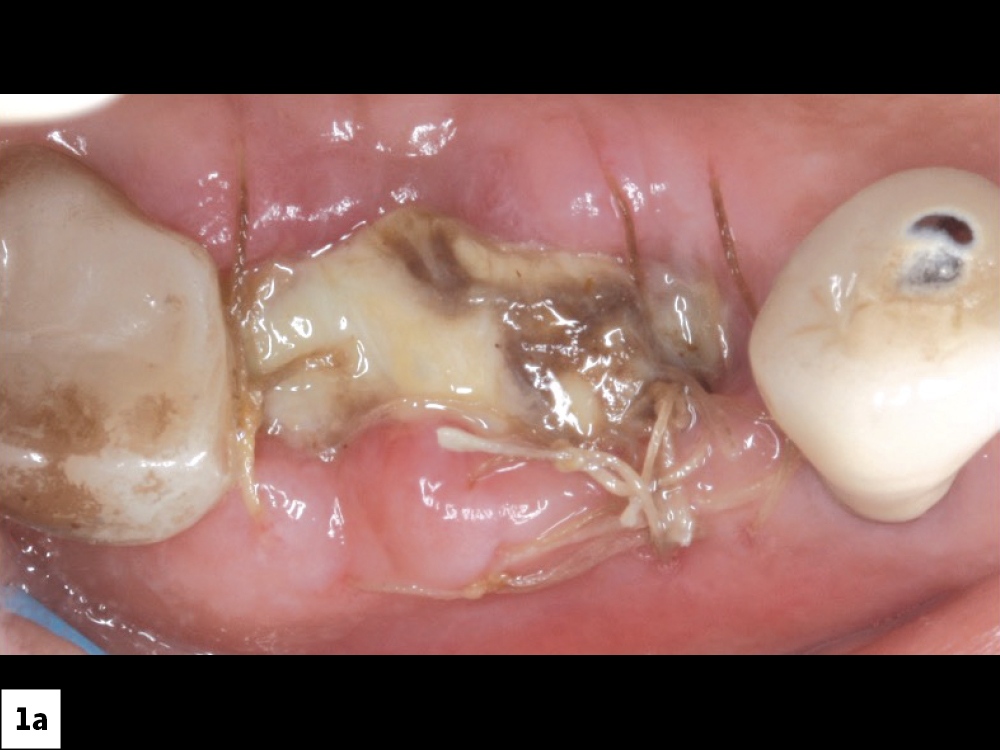

When this wound breakdown occurs, an increased morbidity for dental implant surgery and bone grafting may result because of bacterial contamination (Figs. 1a, 1b). In this article, various techniques and protocols will be discussed to prevent ILO and manage this complication.

Incision line opening: (a) implants, (b) guided bone regeneration procedures.

Figures 1a, 1b: Incision line opening: (a) implants, (b) guided bone regeneration procedures.